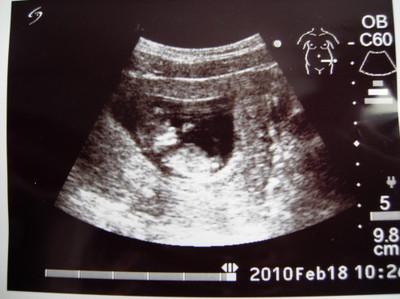

(圖/懷孕週期:11W)

你已經4.5cm了。醫生說你現在長得像外星人,但是身體的軀幹、四肢已經形成。看到你對我們揮動著小手,阿嬤很興奮,把拔覺得很奇妙,不知道馬麻心裡在想什麼。我想馬麻應該常常和你說話吧?只是不知道都說些什麼。